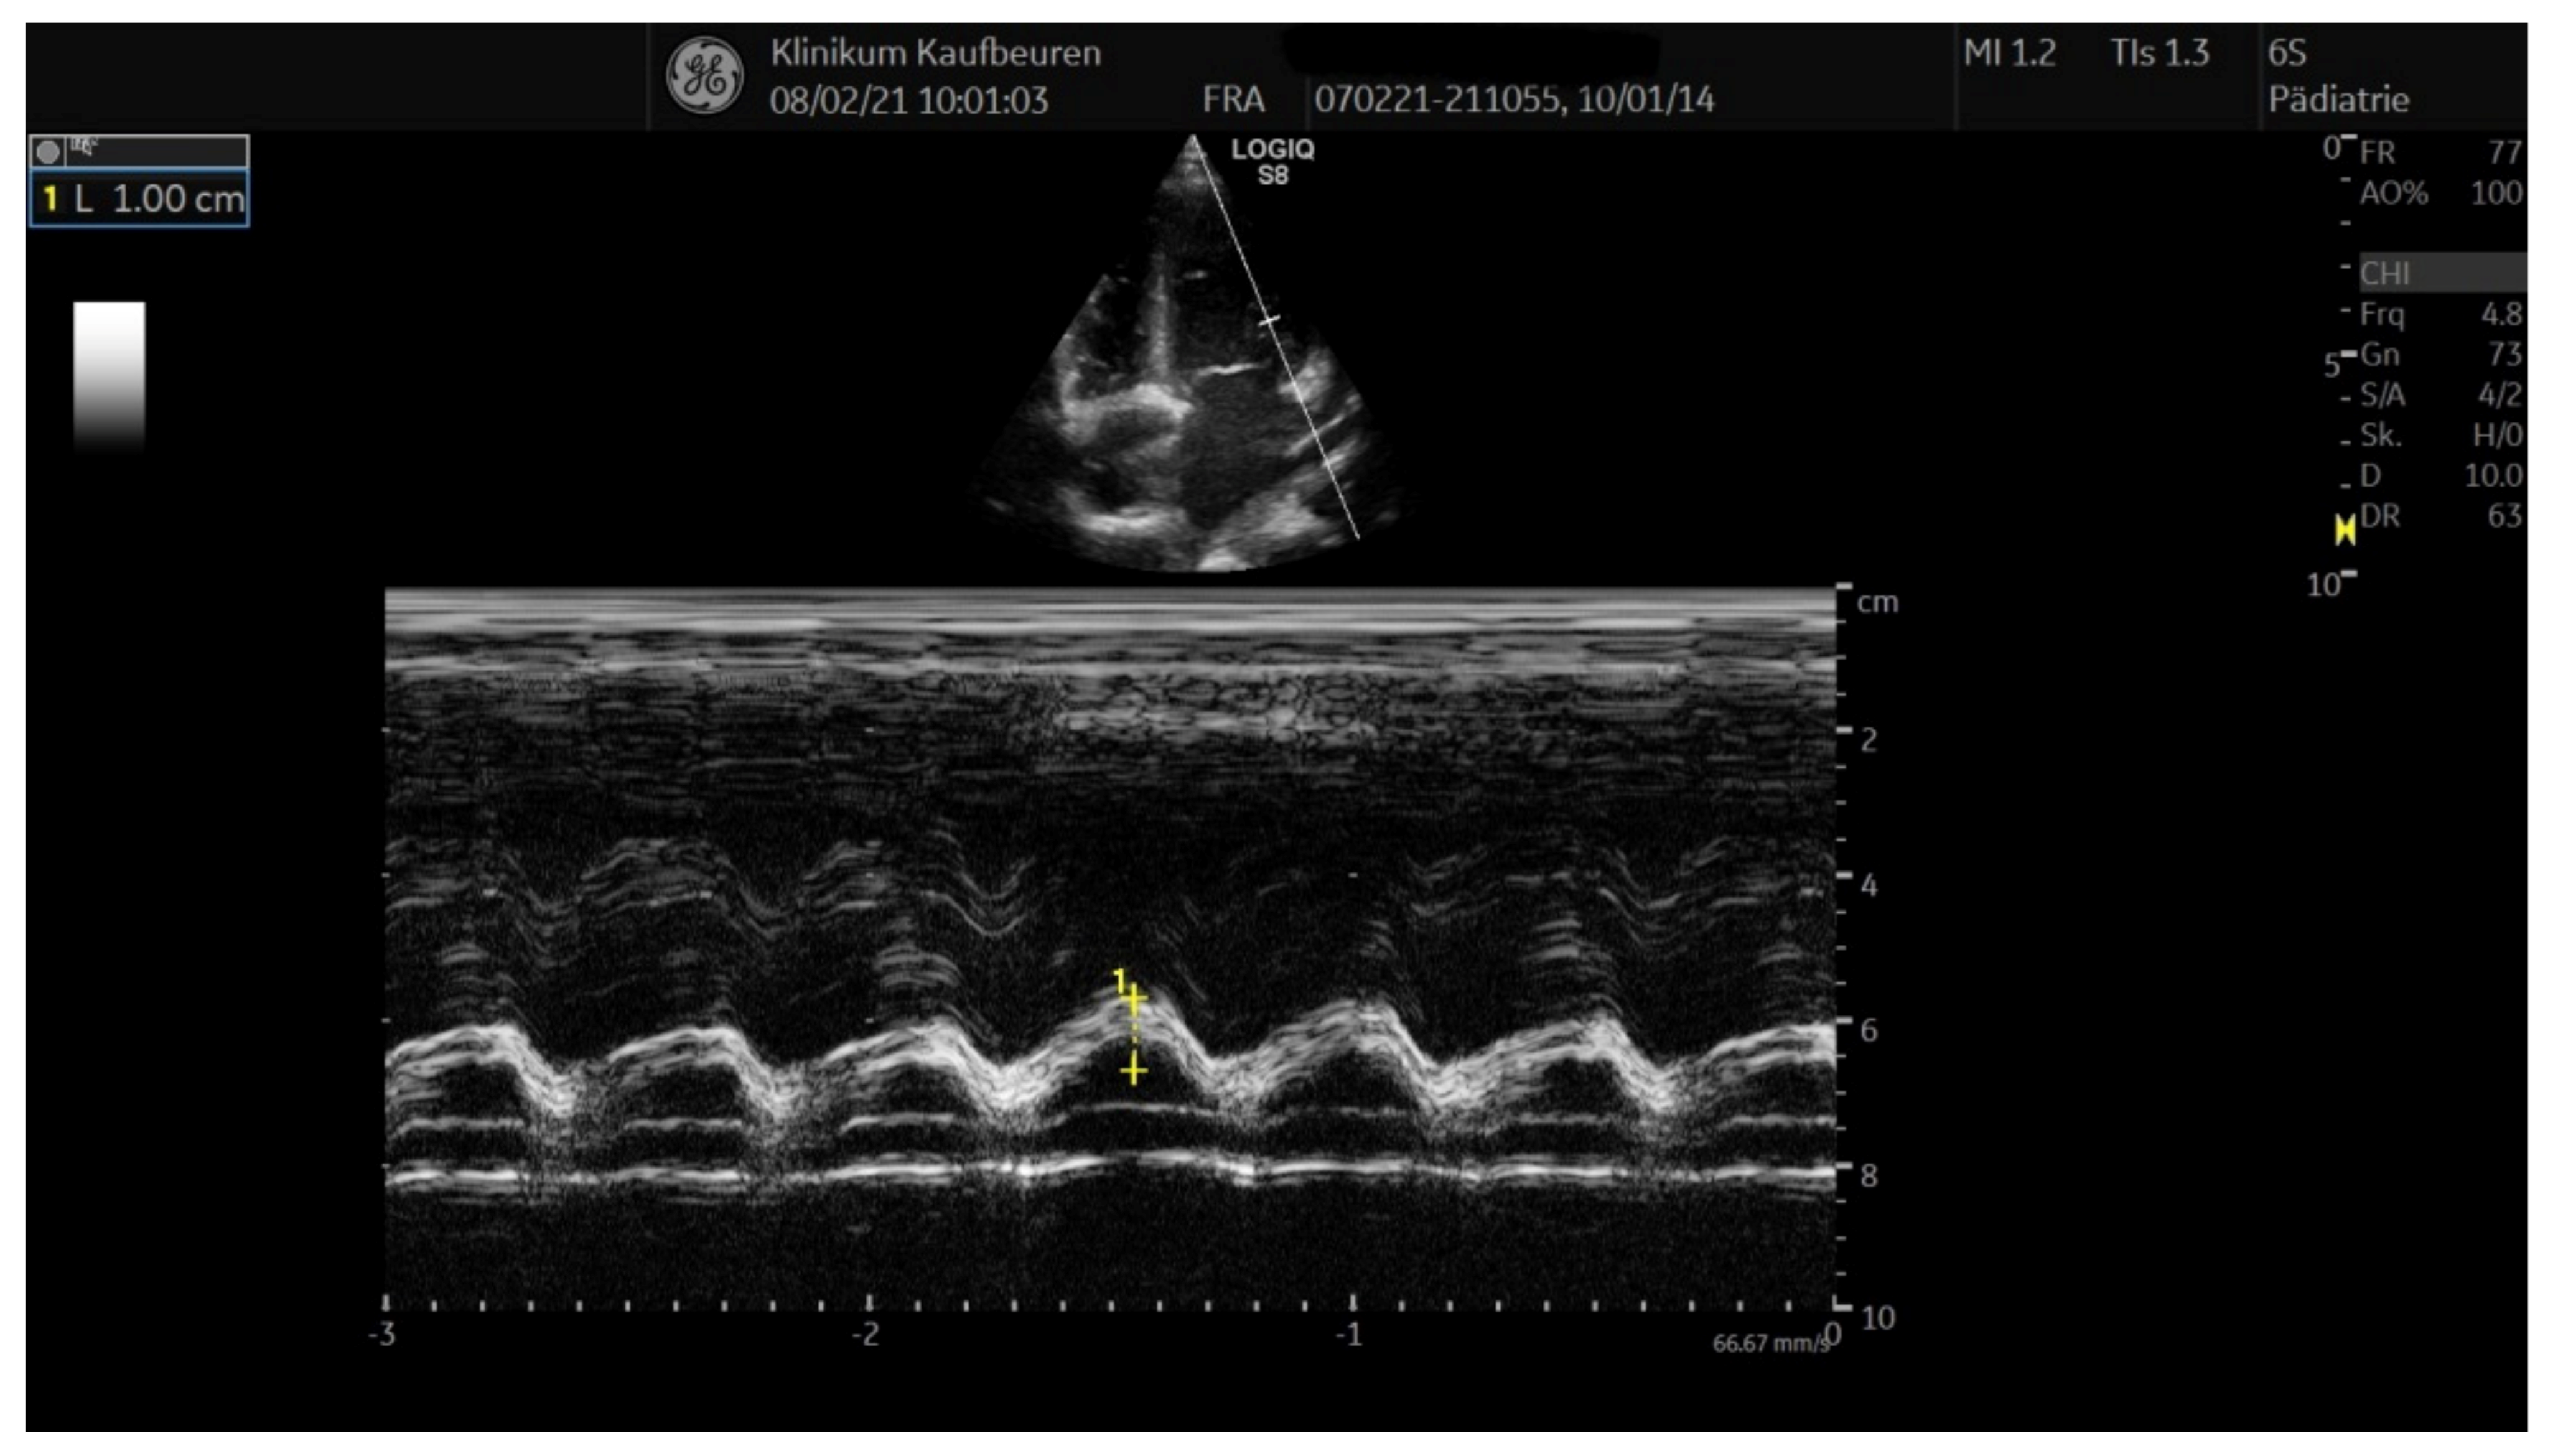

| Patient 1 | Patient 2 | Patient 3 | |

|---|---|---|---|

| LVEF (%) | 81 | 69 | 73 |

| FS (%) | 50 | 39 | 41 |

| MAPSE (cm) | n.d. | 1.67 | 1.5 |

| TAPSE (cm) | n.d. | 2.46 | 2.08 |

| LCA (mm) | 3.7 | 3.2 | 2.8 |

| RCA (mm) | 3.3 | 3.0 | 2.4 |

| Pericardial effusion (mm) | 0 | 3–7 | <3 |

| Pleural effusion (mm) | 0 (both sides) | 0 | 0 |